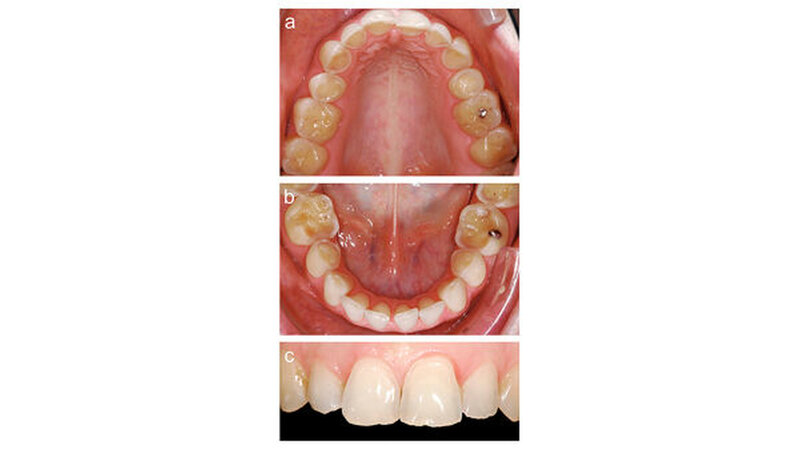

Nach diesen Vorarbeiten wurden Alginatabformungen von Ober- und Unterkiefer genommen und eine Bissregistrierung durchgeführt. Im zahntechnischen Labor wurde die ideale Okklusion im Artikulator bei einer Sperrung der Frontzähne um etwa einen Millimeter aufgewachst. Bei der Anfertigung der Wax-up-Modelle wurden jeweils die Frontzähne und Bereiche der endständigen Molaren nicht aufgebaut. Auf den Modellen wurden für Ober- und Unterkiefer je zwei stabile, lichtdurchlässige Übertragungsschienen hergestellt, die später im Mund der Patientin eine ausreichende Abstützung in der Front und in den nicht aufgewachsten distalen Bereichen gewährleisteten (Abbildung 2).